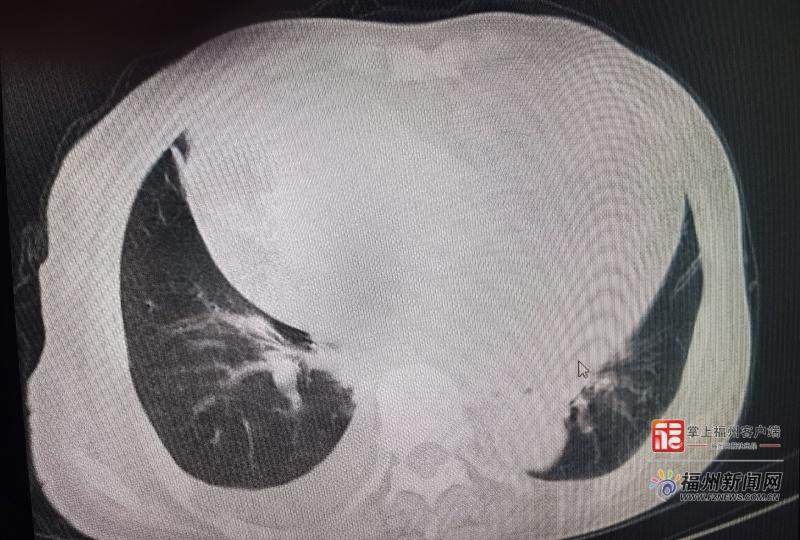

患者影像图。(省老年医院 供图)

该院心血管内科主任医师王世红近日接诊一例78岁的老年女性。该患者术前评估时自称可上四层楼,无典型气促,仅偶有食欲不佳。但深入问诊发现,其上二楼即感双下肢无力,需休息后才能继续。后续检查证实其心脏已明显扩大且功能受损。“这位患者的主观‘正常’掩盖了客观的‘异常’。若非细致追问,极易漏诊。”王世红表示,临床上约40%的老年心衰患者常表现为两周以上不明原因乏力、食欲下降等非典型症状,若误认为是衰老而忽略检查,可能错失治疗良机。